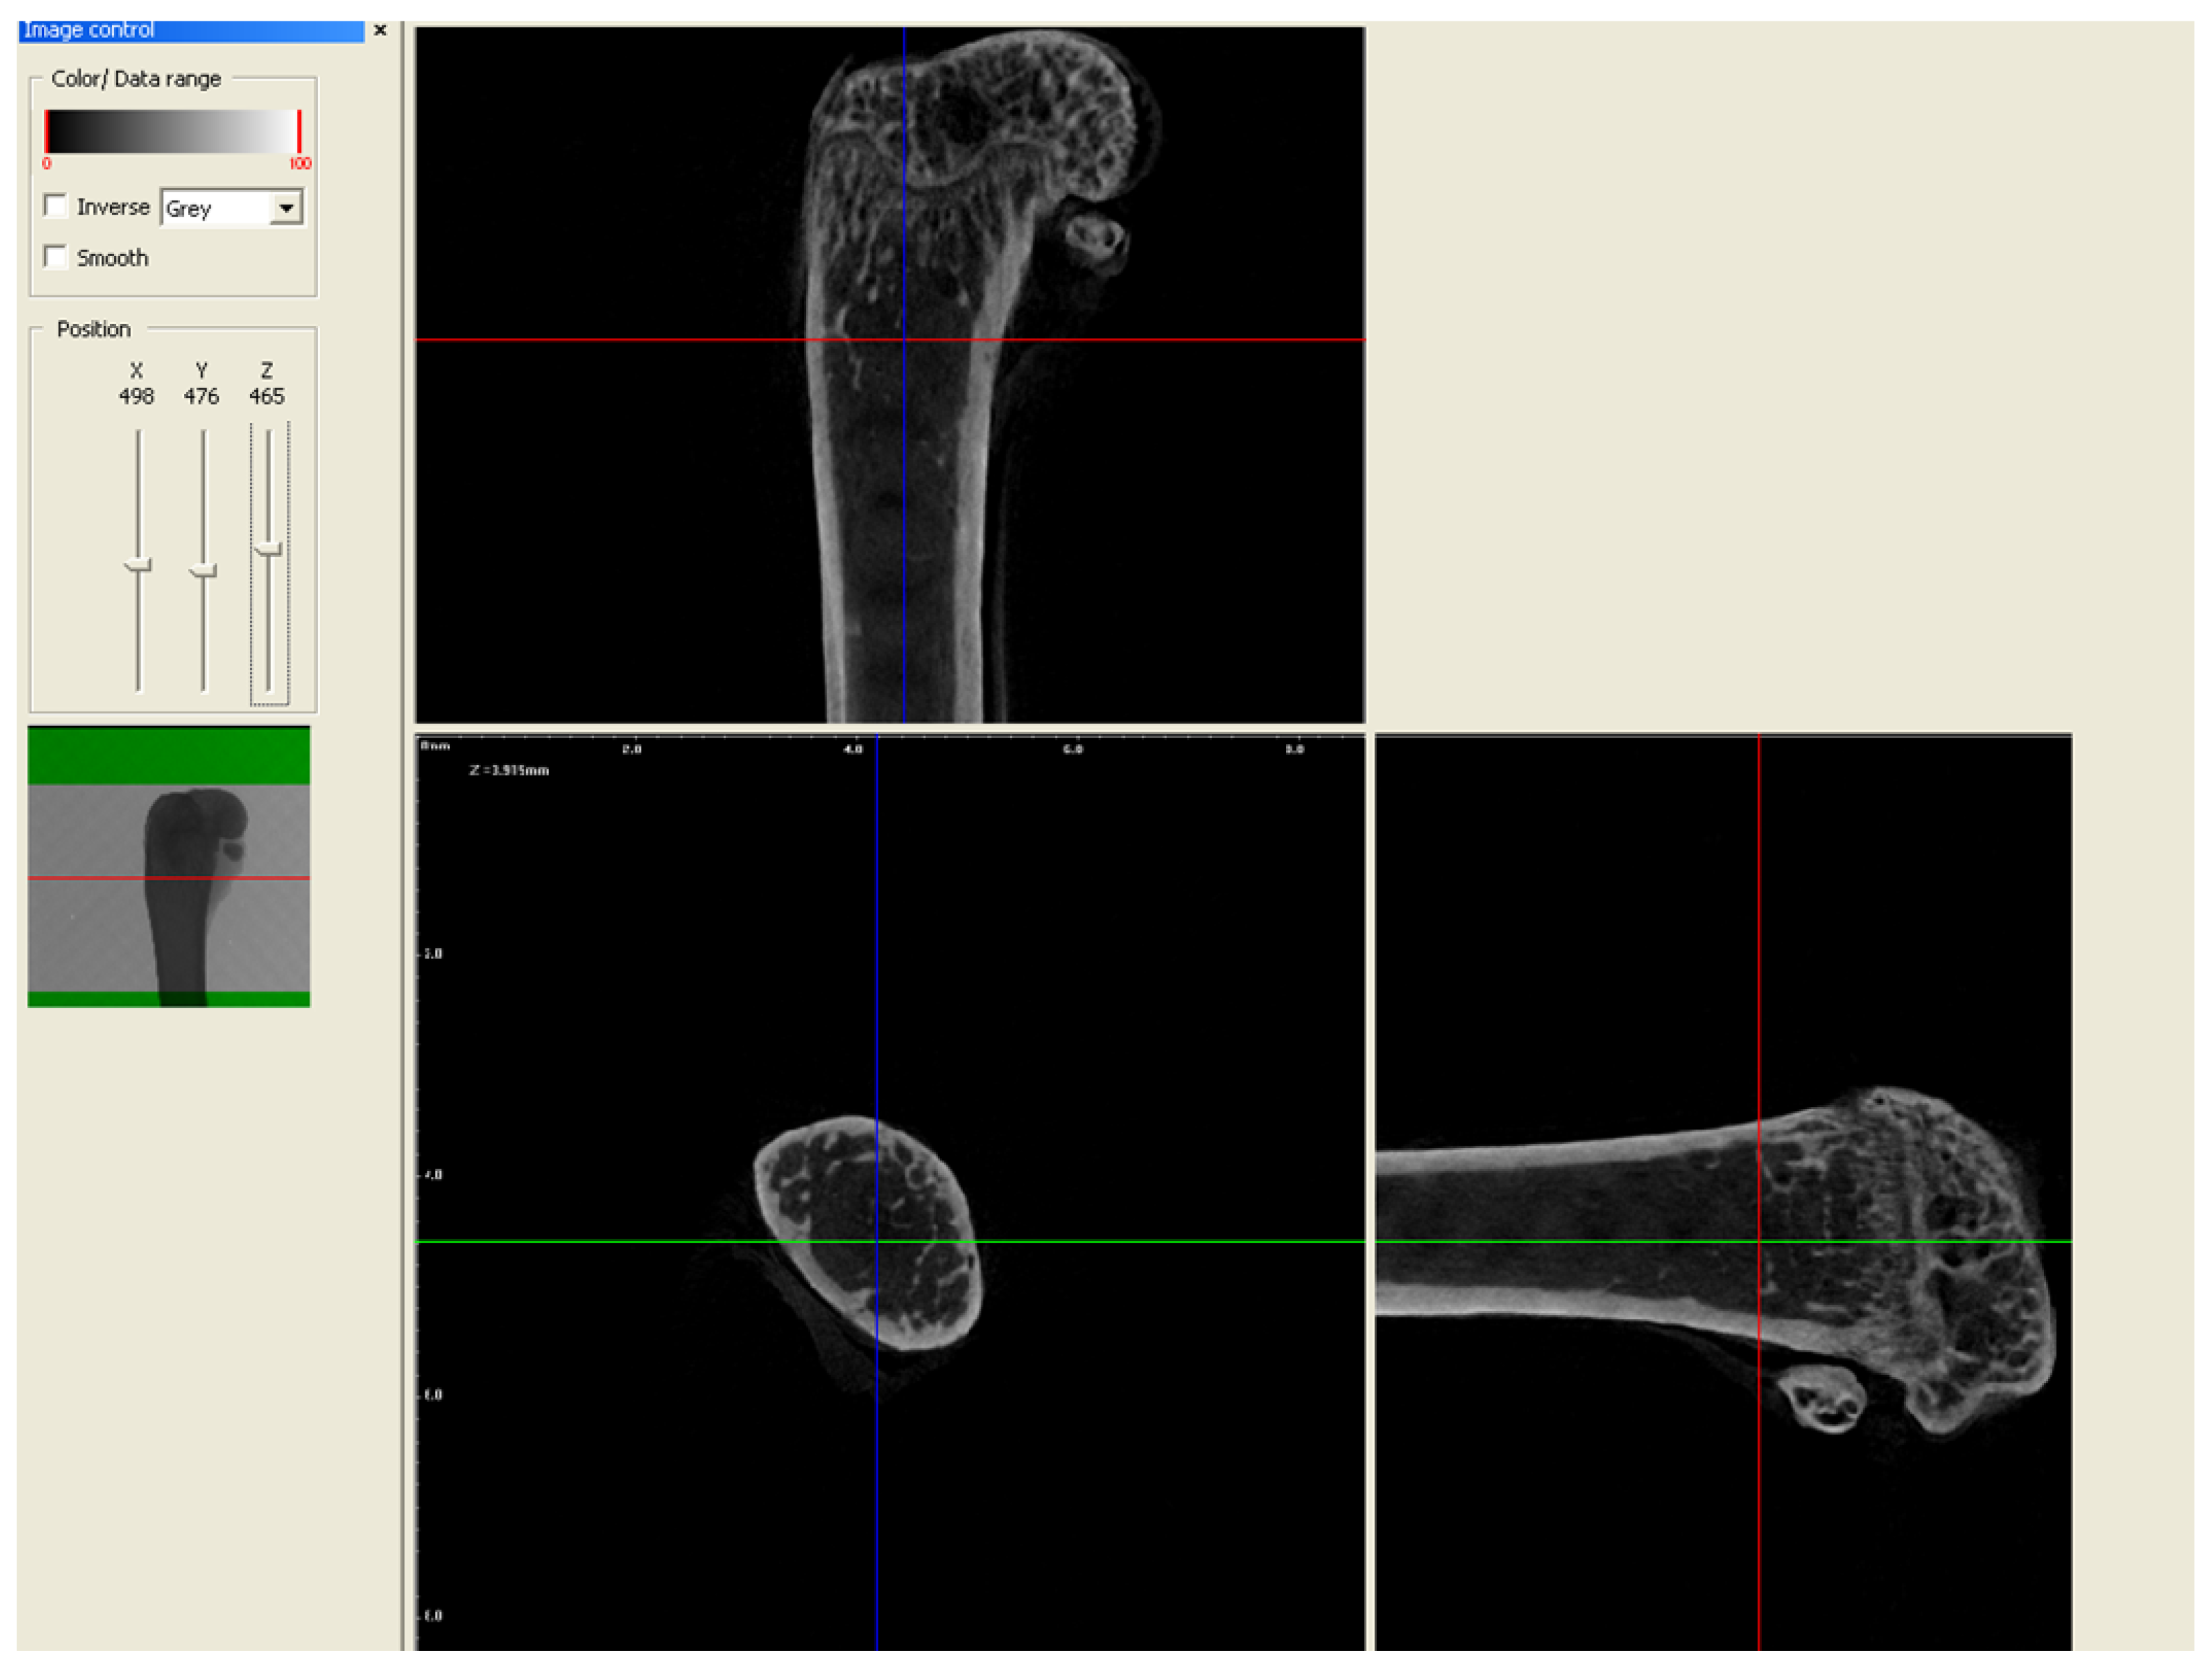

2.2. Micro-CT Analysis

3.3.1. Trabecular Thickness (Tb.Th), Trabecular Number (Tb.N), and Percent of Bone Volume (BV/TV)

3.3.2. Trabecular Separation

3.4. Cortical Bone Area